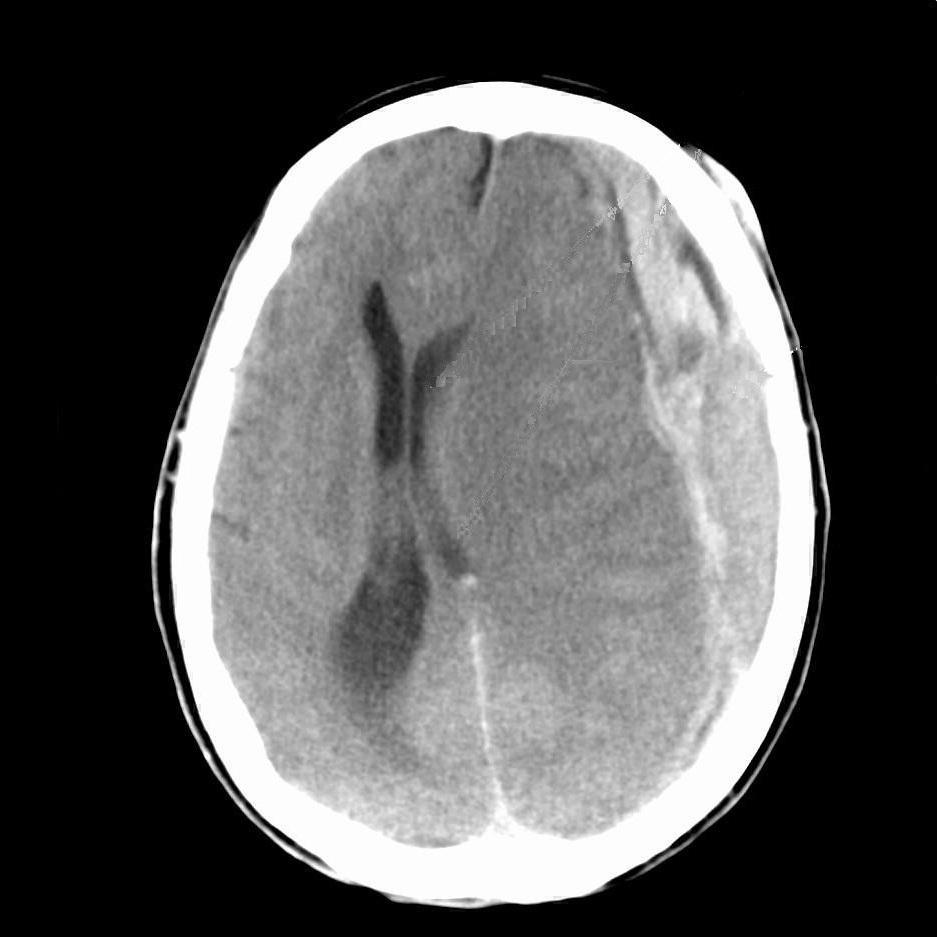

Acute Subdural

Acute Subdural 2